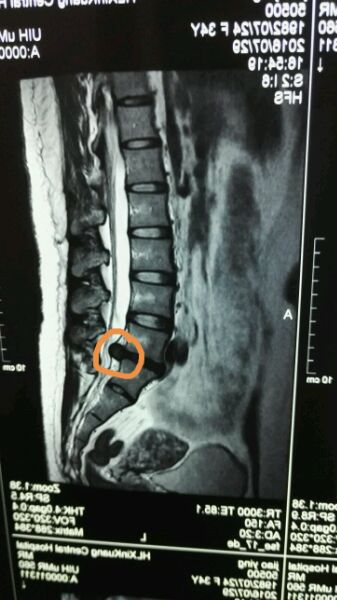

看看我的,突了多少,我觉得我算是吧里突出最大的了,做个磁共振,突出物一清二楚,多清楚啊,目前保守半年无效,山东省立医院明天手术,椎间孔镜,崔新刚主任做,相信他,也相信自己,手术完后一定努力锻炼腰背肌!可不能好了伤疤忘了疼,与突友共勉!!!

上传术后片子对比就知道摘的干不干净了,还有症状是不是椎间盘突出压迫神经导致的要弄清楚,你这个位置在腰骶部,那个地方的椎管是比较宽的,有很多人突出但未必有症状!